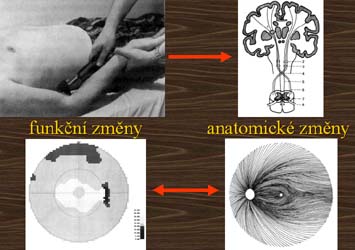

Předpokladem pro použití topické metody je znalost anatomických a funkčních vztahů mezi jednotlivými oblastmi nervového systému. U glaukomu takové vztahy byly již nalezeny, a to vztahy mezi terčem zrakového nervu, vrstvou nervových vláken a výpadky v zorném poli.

Mincler ve svých experimentech s křenovou peroxidázou injikovanou do terče zrakového nervu opic zjistil, že při aplikaci blízko okraje terče tato látka pronikne do okrsku gangliových buněk temporálně od makuly a nepřekročí horizontální čáru. V zorném poli tomuto okrsku odpovídá nasální skok v protilehlé polovině zorného pole. Při aplikaci nad střed terče tato látka pronikne do okrsku gangliových buněk v horní části makulární oblasti a v zorném poli tomu odpovídá paracentrální skotom v protilehlé polovině zorného pole.

Při aplikaci křenové peroxidázy do oblasti od středu terče až k jeho okraji tato proniká do gangliových buněk v obloukovitém okrsku zasahujícím od terče až temporálně od makuly. Na perimetru tomu odpovídá arkuátní skotom v protilehlé polovině zorného pole.

Ze změn terče lze pouze usuzovat na změny zorného pole, zatímco defekty ve vrstvě nervových vláken odpovídají změnám zorného pole s velkou přesností, dokonce jim často i předcházejí.

K reflexům můžeme přirovnat změny zorného pole a k místu poškození nervového systému vrstvu nervových vláken s terčem zrakového nervu. Ale na rozdíl od neurologů, kteří musí vyšetřovat reflexy, které vidí, aby poznali postižení oblasti CNS, kterou nevidí, můžeme postupovat i opačně, neboť vidíme i funkční i anatomické změny současně.